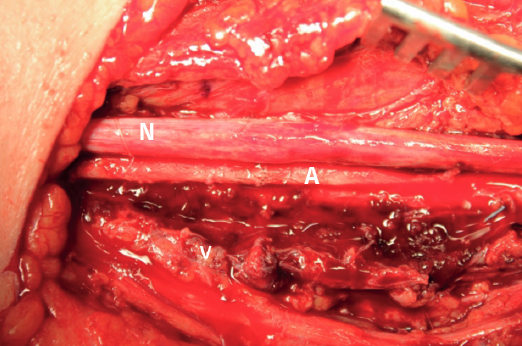

En el quirófano, se realiza incisión en la cara medial del brazo y, tras una disección cuidadosa, se localiza el paquete neurovascular formado por la arteria braquial, el nervio mediano y la vena basílica (Figura 3). Destaca la presencia de un gran hematoma que se reseca, así como el cuerpo extraño causante de la lesión.

La arteria braquial presenta una lesión transfixiante. El nervio mediano se encuentra contundido y de aspecto hemorrágico (Figura 4), secundario a la compresión que ha sufrido.

Se realiza una anastomosis arterial terminoterminal con sutura de 9/0; tras ello, se retira la isquemia y se recupera el flujo arterial normal (Figura 4).